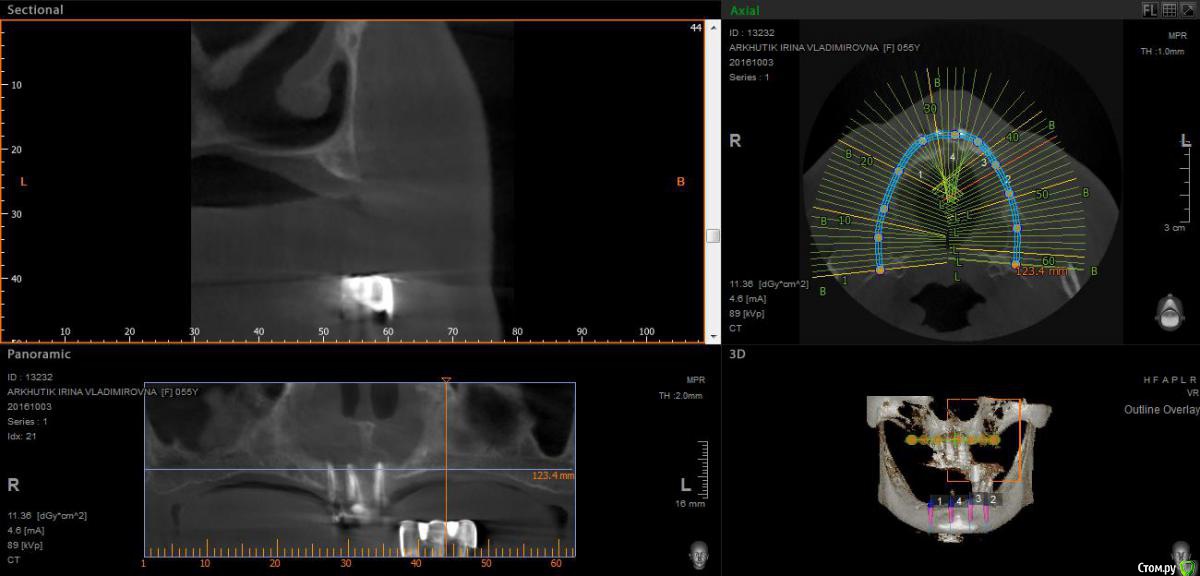

Rusty Опубликовано 5 октября, 2016 Поделиться Опубликовано 5 октября, 2016 Добрый день. К ортопеду обратилась пациентка 55-60 лет с такой ситуацией. Пришла с дочкой, дочь с мамой настаивали на несьемной конструкции, ортопед отправил на кт и вот. Не хочу планировать ей много хирургии, оцените и мой план пожалуйста и буду рад услышать советы по реабилитации пациента. По сути да) просто искал место куда есть возможность поставить, ортопед говорит тогда балка либо локаторы Ссылка на комментарий

Rusty Опубликовано 5 октября, 2016 Автор Поделиться Опубликовано 5 октября, 2016 На н/ч балка? Какие измерения в дист отделах? На в/ч мало четырёх. По три бы.На н/ч балка, в дистальных отделах над каналом около 3мм. На вч условий для установки больше 4 не нашел) Ссылка на комментарий